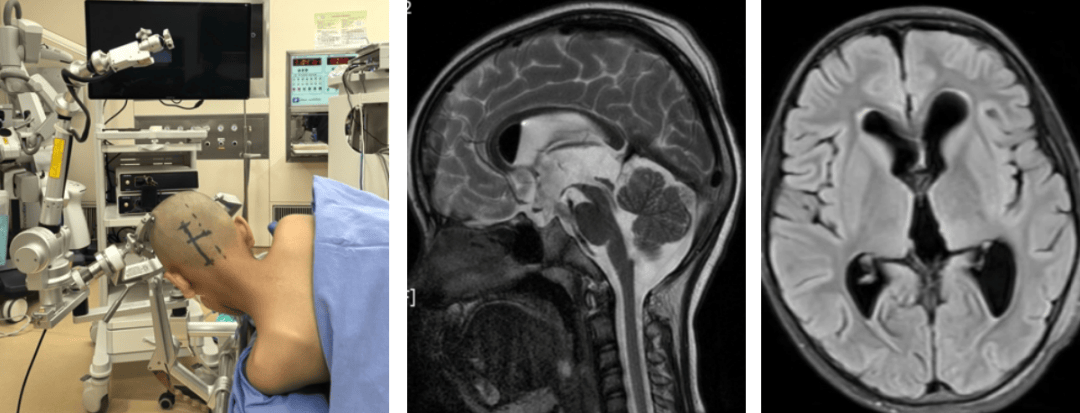

我女儿都了松果体囊肿,请问医生..

松果体囊肿是在神经影像检查中经常发现的一种病变,绝大多数松果体囊肿属于先天性静止期囊肿,也就是这些囊肿本身并不引起明显的症状,也不严重所以临床上多数情况下会告知患者定期复查,比如一年以后做核磁,如果囊肿没有任何变化,...